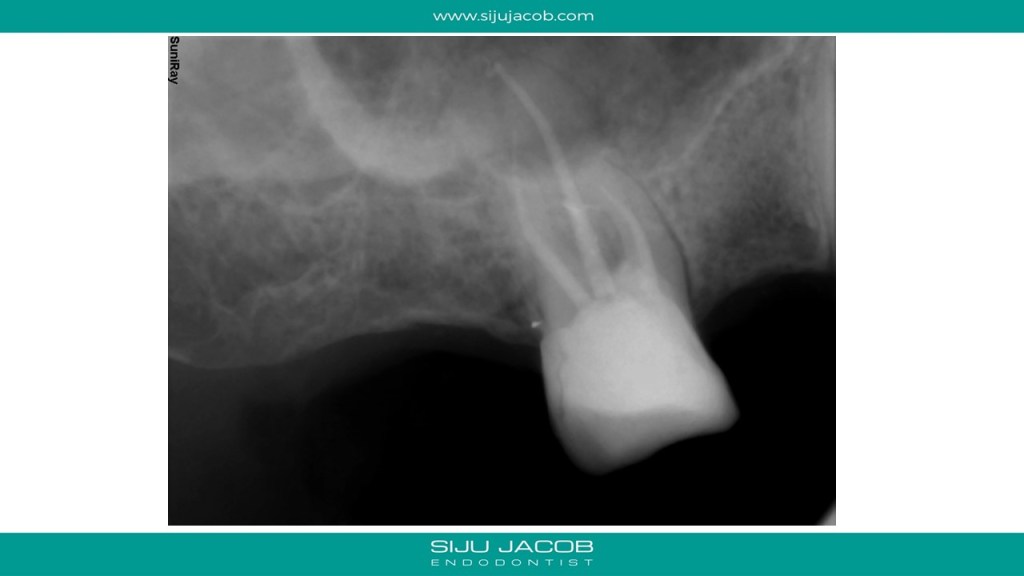

Here’s a trick i use to prevent the MTA from slipping into the canal when the perforation is very close to the canal. This maxillary first molar had a missed Mesio-buccal canal with a perforation. After locating the mesio-buccal canal and cleaning it, the canal was filled with calcium hydroxide. A gutta percha cone was then placed into the canal and sheared off at the coronal level. The perforation was sealed with MTA, a moist cotton pellet was placed in the pulp chamber and the access closed with GIC. After 1 week, the temporary filling is removed and the MTA checked for hardening. The gutta percha placed in the MB canal is then removed with a rotary ni-ti file. The calcium hydroxide placed in the canal is removed and the canal is obturated with gutta percha. A composite core is placed.